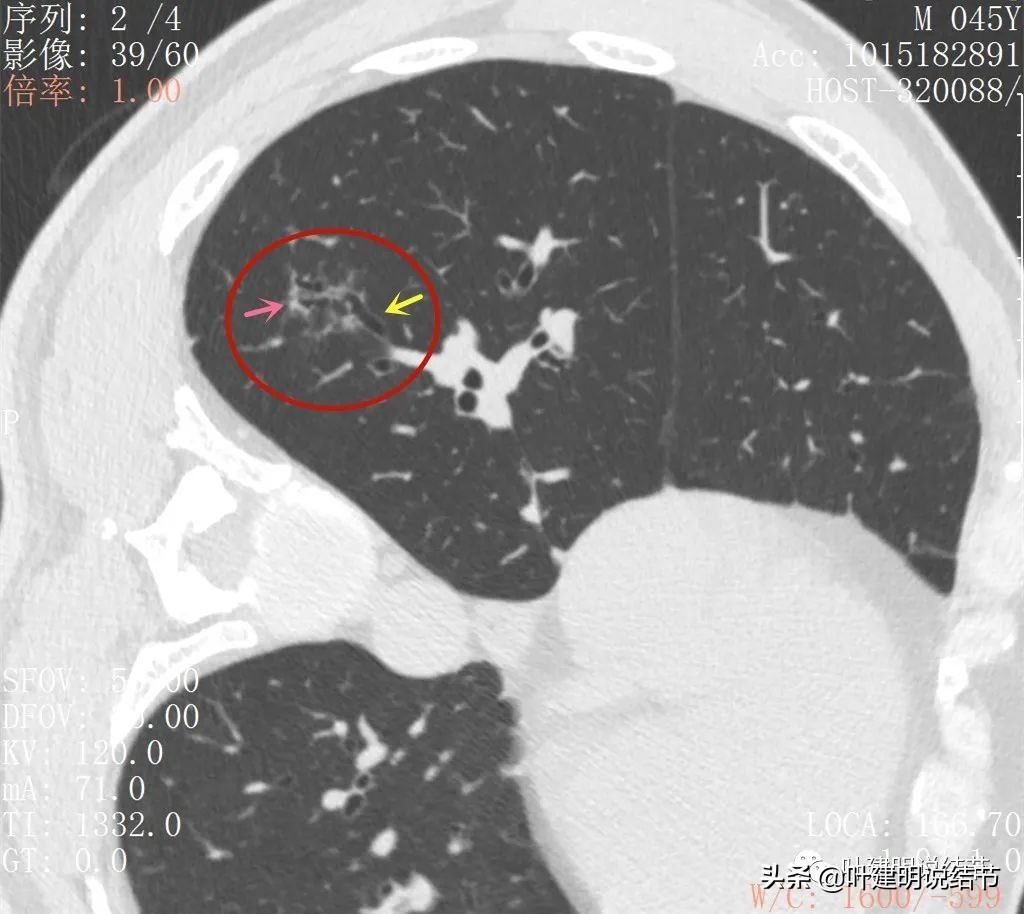

再来看薄层扫描:

病灶感觉很散在,但内部有扩张的细支气管(黄色箭头)、边缘略显不清(绿色箭头),部分有偏实性(粉色箭头)。

边缘血管异常增粗(桔色箭头),边缘显糊(绿色箭头),细支气管扩张(黄色箭头)

病灶似乎非圆形或类圆形,扩张的细支气管壁密度偏高(蓝色箭头),感觉比较僵硬(黄色箭头),病灶轮廓显模糊(黄色箭头)

扩张细支气管壁密度较高,病灶轮廓显糊